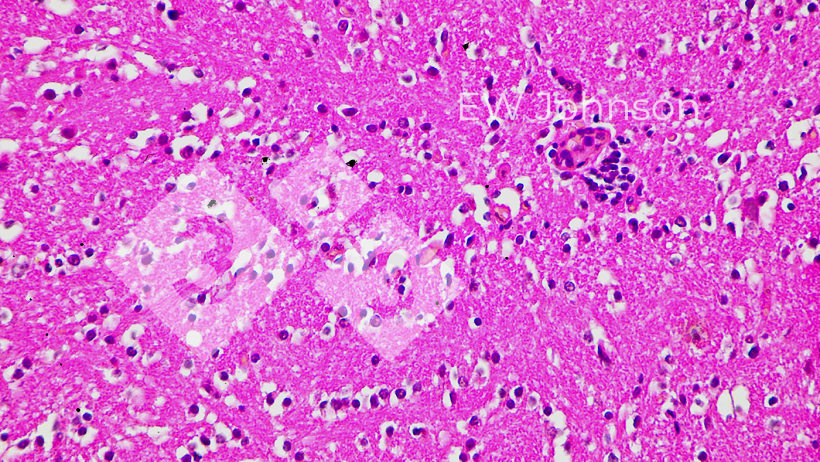

Wynik badania PCR był ujemny dla PRRS, rzekomego pomoru świń (PRV, choroba Aujeszky'ego), cirkowirusa świń PCV2 i PCV3, klasycznego pomoru świń (CSF) i afrykańskiego pomoru świń (ASF). Stado było wolne od PRRS, PRV, CSF i ASF przed tym zdarzeniem. PCR dla Getahvirusa w płucach prosiąt był silnie dodatni. Badanie histopatologiczne wykazało ciężkie śródmiąższowe zapalenie płuc (ryc. 3) i włóknisto-krwotoczne zapalenie opon mózgowych (ryc. 4). Postawiono diagnozę okołoporodowej choroby getahvirusowej. Gospodarstwo zostało poinformowane, że choroba ta jest przenoszona głównie przez komary i wprowadzono środki kontroli. W gospodarstwie nie wystąpiły dalsze przypadki ani objawy kliniczne, a produkcja powróciła do normalnego poziomu.

Ryc. 4. Zapalenie mózgu z zapaleniem naczyń, saturacją i neuronofagią